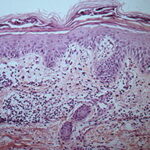

Histopathology. The earliest change consists of acantholysis in the upper epidermis, within or adjacent to the granular layer, leading to a subcorneal bulla in some instances . More commonly, enlargement of the cleft leads to detachment |

of the stratum corneum without bulla being seen. The number of acantholytic keratinocytes is usually small, often requiring a careful search to identify them. Secondary clefts may develop, leading to detachment of the epidermis in its mid level. These clefts may extend to above the basal layer, rarely giving rise to limited areas of suprabasal separation. In the setting of a subcomeal blister, dyskeratotic granular keratinocytes are diagnostic for this disorder. Eosinophilic spongiosis may be prominent with intraepidermal eosinophilic pustules. Thus, the histologic features of pemphigus foliaceus may have three pattems: {a} eosinophilic spongiosis; {b} a subcorneal blister, often with few acantholytic keratinocytes; and {c} a subcorneal blister with dyskeratotic granular keratinocytes , diagnostic of this disorder. The character of the inflammatory infiltrate is variable and depends on the age of the lesion, whether a blister is present, whether the superficial portion of the epidermis has been detached, and whether there is impetiginization or necrosis of the blister roof. |